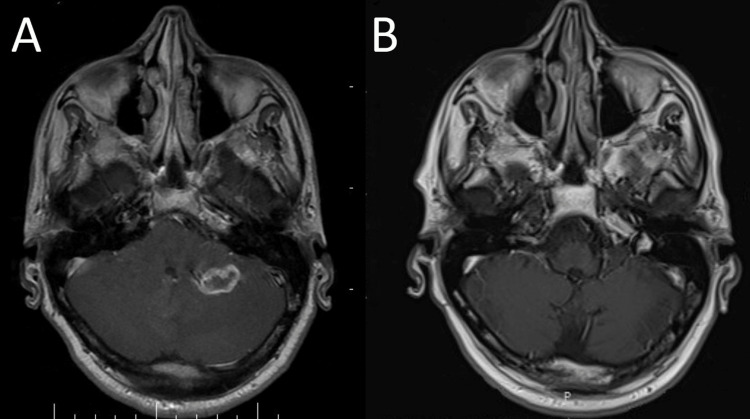

Open right radical nephrectomy was performed in November 2019 and the histopathologic diagnosis revealed clear cell type RCC with massive necrosis and no sarcomatoid differentiation along with invasion to the renal pelvis, adrenal gland, omental fat, and diaphragm. Accordingly, the patient was commenced on adjuvant sunitinib 50 mg on the 3/1 schedule (50 mg once daily for three consecutive weeks on treatment followed by one-week-off). Following four months of treatment with sunitinib, the patient became icteric and developed a progressive headache. Further evaluations discovered multiple masses in the renal fossa and abdominal wall, multiple round lesions in the right hepatic lobe, and a few right pleural-based nodules. He was also found to have two enhancing lesions (20×15 mm and 5×3 mm) in the posterior fossa of the brain consistent with metastatic disease (Figure 2).

Due to the failure of first-line treatment with sunitinib, treatment was switched to nivolumab 3 mg/kg (240 mg) administered every two weeks. He also received palliative whole-brain radiation therapy (WBRT) to a total dose of 35 Gy delivered during 14 fractions. After four months of treatment with nivolumab, fluorodeoxyglucose (FDG) – positron emission tomography (PET)/CT scan was obtained and it revealed complete resolution of metastatic lesions in the brain and lungs as well as a reduction in the size and the number of lesions in the liver, without the appearance of any new lesions (Figure 3).